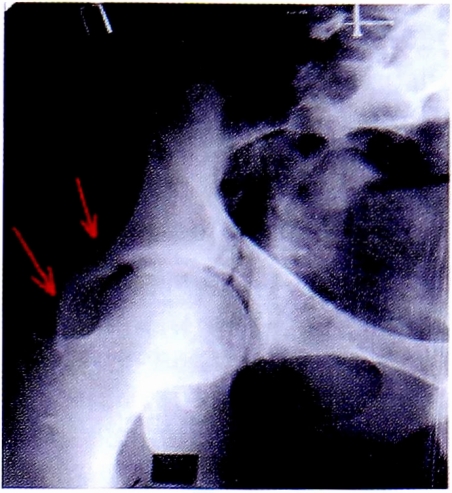

После выполнения прицельной рентгенографии в косой подвздошной проекции по методике НМИЦ TO, выявлена линия перелома, проходящая через крыло подвздошной кости, сурсил и нижние отделы передней колонны. Также на прицельной рентгенограмме отчетливо видна интактность задних отделов вертлужной впадины (рис. 13).

Рис. 13. Рентгенография левого тазобедренного сустава в косой-подвздошной проекции, выполнена по методике НМИЦ ТО. Стрелками показана линия перелома в местах прохождения через визуализируемые структуры вертлужной впадины.

Fig. 13. Iliac oblique view made CITO method. Arrows shows fracture lines crossing acetabulum.